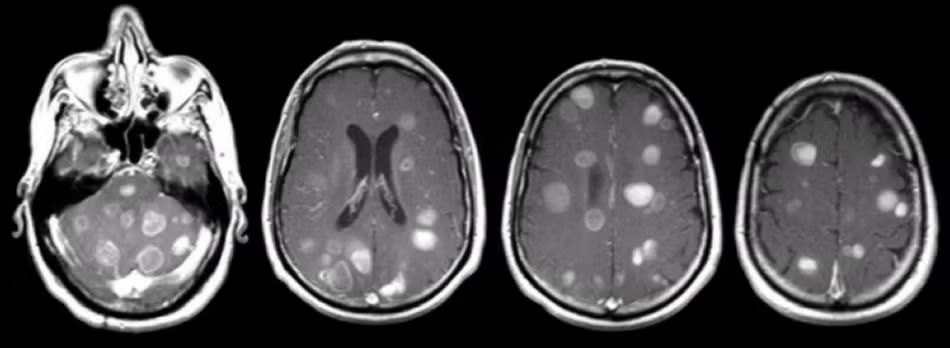

Doctors may recommend imaging tests like MRI or CT scans to get a clearer picture.